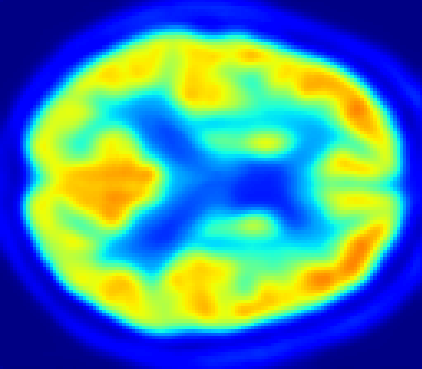

In Fig. 4, the attention maps of the U-PET are shown for multiple examples. On the one hand, the attention map of the skip connection (AttMap skip) highlights details of the brain structure, which is in agreement with the assumption that the network has to transform the specific structures of the MRI scan into the PET modality. On the other hand, the attention gates used for the classification task rather focus on more specific regions. One can observe a trend that the attention maps used for classification tend to highlight regions which have a low uptake in the PET. Since areas with a lower uptake in the PET correspond to areas with lower functional activity (hypometabolism), this focus area of the network seems reasonable with respect to the classification task.